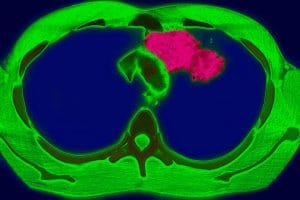

La tubercolosi – La tubercolosi è una malattia infettiva causata da un batterio. Il contagio può avvenire tramite saliva, starnuto o colpo di tosse. La malattia attacca solitamente i polmoni, ma può colpire anche altre parti del corpo.

L’esame preliminare più diffuso per diagnosticare una forma tubercolare è il test di Mantoux: la reazione positiva a questo esame indica che il sistema immunitario è già venuto a contatto con il batterio della tubercolosi. Spetta al medico decidere la terapia più idonea sulla base degli esami e della storia clinica del paziente.